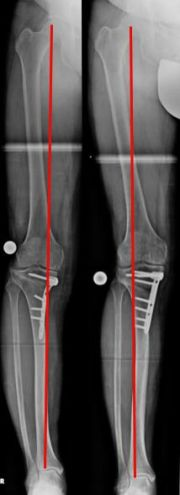

Beidseitige, zuklappende Korrekturosteotomie, kniegelenksnah am Oberschenkel bei X-Bein und fortgeschrittener Arthrose (Bild 9).

Bemerkenswert ist die „Öffnung“ des äußeren Gelenkspaltes, am rechten Bein, durch die Lastumverteilungsmaßnahme. Korrekturen wie diese adressieren nicht nur Knie- sondern auch Beinschmerz.

Sie dienen gleichzeitig der Vereinfachung einer später eventuell notwendigen Versorgung mit einer Gelenkprothese.